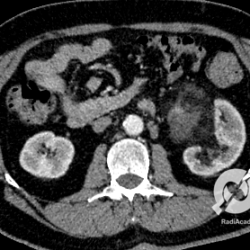

Uma tomografia de uma paciente com dor lombar à direita, e apresentando dor à percussão lombar. A tomografia mostra um rim aumentado de volume, com densificação adiposa perinéfrica inflamatória (este aumento de densidade da gordura envolvendo o rim). Este é um corte com contraste e é bem evidente quando comparamos os rins, que o lado direito capta o contraste de modo heterogêneo, com múltiplas áreas hipoatenuantes de baixa captação esparsas. Estas imagens são de natureza inflamatória, confirmando uma pielonefrite aguda. Não existe dilatação calicinal aqui.